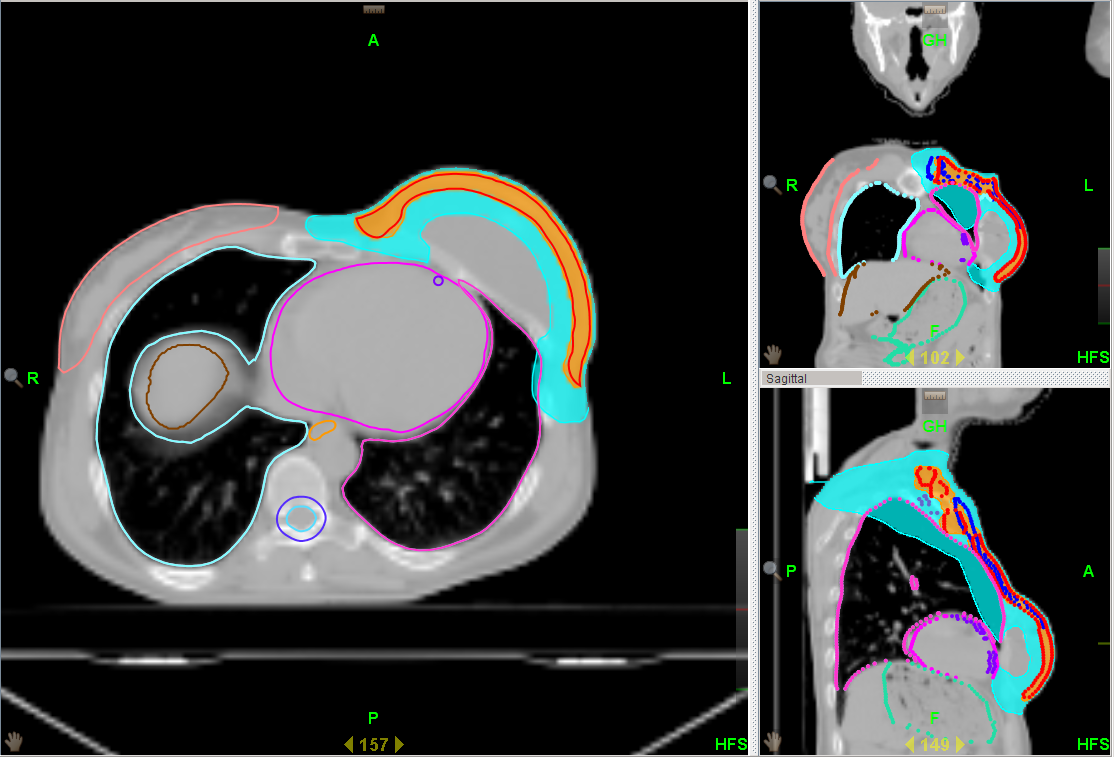

Al fine di ridurre intensità e frequenza degli effetti collaterali dovuti al trattamento radioterapico in seguito ad una ricostruzione mammaria, viene utilizzata la tecnica HALFMOON (semiluna), che consente di modulare l’irradiazione sulla mammella ricostruita dopo una mastectomia e risparmia protesi/espansore, garantendo la stessa efficacia terapeutica delle tecniche tradizionali (fig. 1).

| Fig. 1 | Fig. 2 |